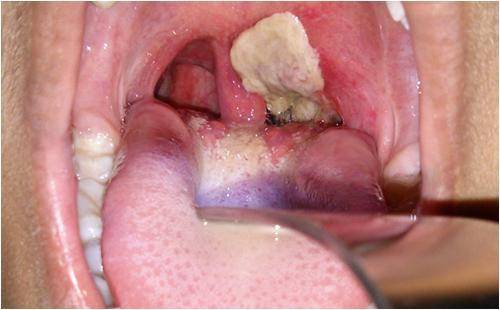

白喉是由白喉棒状杆菌(Corynebacterium Diphtheriae)引起的一种感染。通常在发生暴露后2至5天出现症状和体征,其严重程度为轻度到重度不等。症状的出现通常较为缓慢,初始症状为咽喉痛和发热。严重情况下,细菌会产生一种毒物(毒素),在咽喉后部形成厚厚的灰色或白色斑块。这会阻塞呼吸道,导致呼吸或吞咽困难,并出现犬吠样咳。颈部可能在一定程度上由于淋巴结肿大而出现肿胀。

白喉如何诊断?白喉的临床诊断通常依赖于覆蓋咽部的灰色渗出物(假膜)。虽然建议对疑似病例开展实验室检查,以达到确诊目的,但应立即启动治疗。